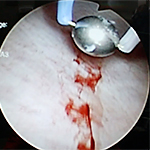

- ハンナ病変を認める場合、電気やレーザーによる焼灼術が行なわれ、疼痛に対しては有用な治療法と考えられています。

- ハンナ病変に対する電気焼灼術は、疼痛に対しては有用な治療法と考えられています。

(術後速やかに疼痛は減少し、治療効果は12ヶ月以上持続)